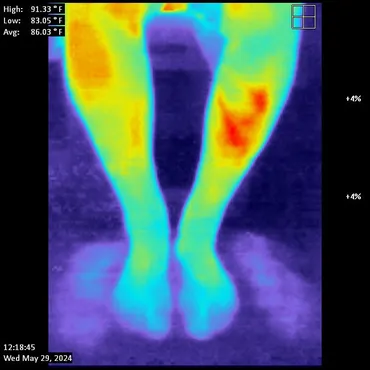

- Thermography used to monitor your response.  Non-invasive technology that shows your circulation as your care progresses.

Therm Hands                                    Therm Legs

Hand Thermography showing cold left hand                                    Foot Thermography showing poor circulation

In Office Case

A 75 year old male started care in July, 2024 for symptoms of lumbar spinal neuropathy.  He had the usual symptoms including pain, burning and

numbness in his legs and feet.  It also affected his balance which is very common due to the interference of nerve signals traveling from the feet and legs

to the brain.  Left untreated, this condition causes a slow death of tissue, nerves and blood vessels hence affecting the communication between the legs /

feet and the brain.  The before and after thermal images tell the story.

JC Pre Thermal                                      JC Thermal Post

Before SoftWave: Blue in the toes indicates poor circulation                    6 Weeks of SoftWave: Red indicates healthy, normal circulation